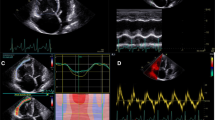

Transesophageal echocardiography exams (diagnostic studies performed by cardiologists or intraoperative exams performed by anesthesiologists) were retrieved from hospital archives. Exams needed to contain one good quality video loop from each of the three following midesophageal views: four-chamber, two-chamber, and long-axis.

Each exam in the PLM included three looping video clips showing the four-chamber, two-chamber, and long-axis views, simultaneously, side by side, for up to 20 sec (see eVideo as ESM). For each exam, participants had to enter their estimation of the LVEF as an integer between 0% and 100% as soon as they could. The three clips disappeared from the screen if no response was provided within 20 sec, and the learner had to give an answer before receiving feedback. This brief feedback consisted of the expert consensus rating, displayed on screen together with the looping clips for an additional ten seconds. The maximum time to complete the 96 PLM exams was therefore 48 min.

As in Romito et al.,12 we created two blocks of 20 exams (A and B) for testing purposes. Each block consisted of five exams each of LVEF < 30%, LVEF 30–39% LVEF 40–49%, and LVEF > 49%. Visual presentation, random ordering, and prompting during testing were identical to those used in PLM training. Nevertheless, no feedback was provided during testing.